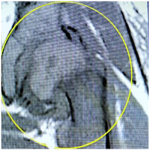

Protocolo para la atención del trauma no accidental en la población infantojuvenil: aspectos radiológico y traumatológico

Bibiana Dello Russo, Mónica Galeano, Florencia D´Adamo

Resolución del caso